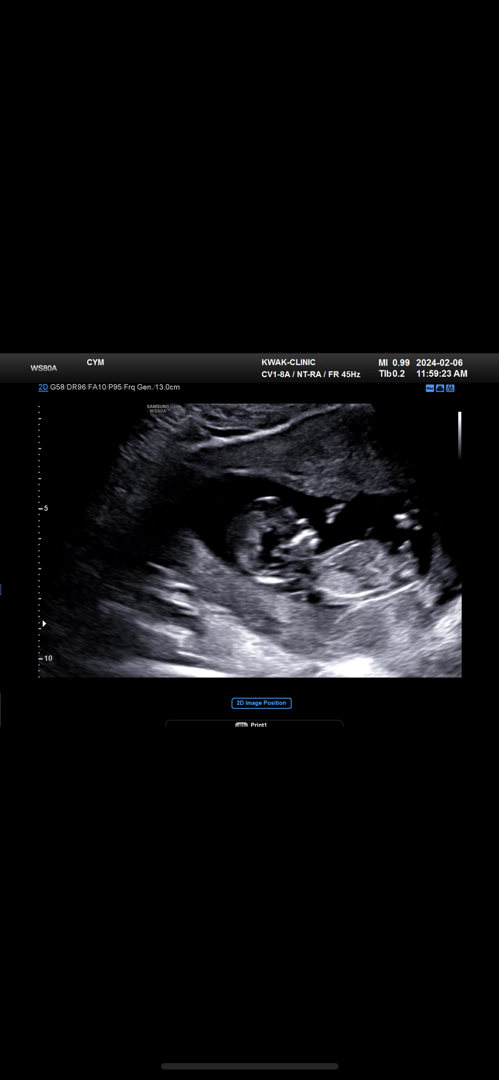

12주 각도법 보이실까요? 궁그매용

12주차 3일이에요! 각도법으로 성별 보이시나용 ㅎㅎ

아들에 한표요!